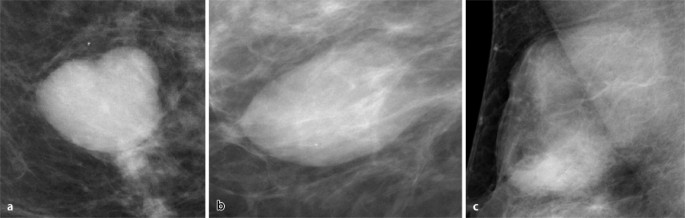

Fibroadenom Sonographisch typisches Fibroadenom mit länglichovaler, gelappter Form bei insgesamt glatter Berandung Das Fibroadenom ist ein gutartiger Tumor der Brust und bedarf in dieser typischen Ausprägung keiner Biopsie, sollte aber über einen kurzen Zeitraum kontrolliert werden. Gutartige Brusttumoren sind Geschwulste der weiblichen Brust, die – je nach Tumorgröße und art – auch verschiedene Symptome hervorrufen können Fibroadenome machen meist keine Beschwerden, da sie in der Regel nicht schmerzhaft sind Die betroffenen Frauen erstasten die harten Knoten meist zufällig oder bei der Selbstuntersuchung der BrustBei sehr schlanken Frauen und wenn der Tumor. Das Fibroadenom meldet sich als „Klassiker“ unter den gutartigen Tumoren der Frau vor der Menopause zumeist sind jüngere Frauen unter 40 Jahren betroffen, mit einem Altersgipfel von ca 25 Jahren Der Tumor ist ein gutartiger Mischtumor, der von der Frau meistens ertastet werden kann.

Ein gutartiger Tumor in der Brust ist eine harmlose Gewebsveränderung und entwickelt sich nur äußerst selten zu einem bösartigen Tumor Nur jedes tausendste Fibroadenom entwickelt sich zu Brustkrebs Trotzdem sollte bei einem gutartigen Tumor die Brust regelmäßig von einem Arzt untersucht werden. Fibroadenom Sonographisch typisches Fibroadenom mit länglichovaler, gelappter Form bei insgesamt glatter Berandung Das Fibroadenom ist ein gutartiger Tumor der Brust und bedarf in dieser typischen Ausprägung keiner Biopsie, sollte aber über einen kurzen Zeitraum kontrolliert werden. Aus diesem Grund wurde angenommen, dass sie das zukünftige Risiko eines bösartigen Tumors nicht erhöhten Die Wissenschafter untersuchten Biopsieproben von 9087 Frauen zwischen 18 und 85 Jahren mit gutartigen Knoten in der Brust, die zwischen 1967 und 1991 in der Klinik behandelt worden waren.

Fibroadenom Das Fibroadenom ist die häufigste Ursache für eine gutartige Veränderung der Brust vor der Menopause (Wechseljahren)Es handelt sich dabei um einen vom Lobus ausgehenden Mischtumor Der Altersgipfel liegt zwischen 25 und 40 Jahren Die Einnahme oraler Kontrazeptiva („Pille“) über längere Zeit senkt das Risiko für ein Fibroadenom. Fibroadenom Brust Symptome mehr als 2 cm haben oft eine unregelmäßige runde Form, eine klare, gleichmäßige oder unebene Kontur Je größer die Größe und Dauer des Vorhandenseins von Fibroadenomen ist, desto häufiger wird der echoreiche Rand aufgrund der Degeneration des umgebenden Gewebes bestimmt. Wann bildet sich ein Fibroadenom von alleine wieder zurück?.